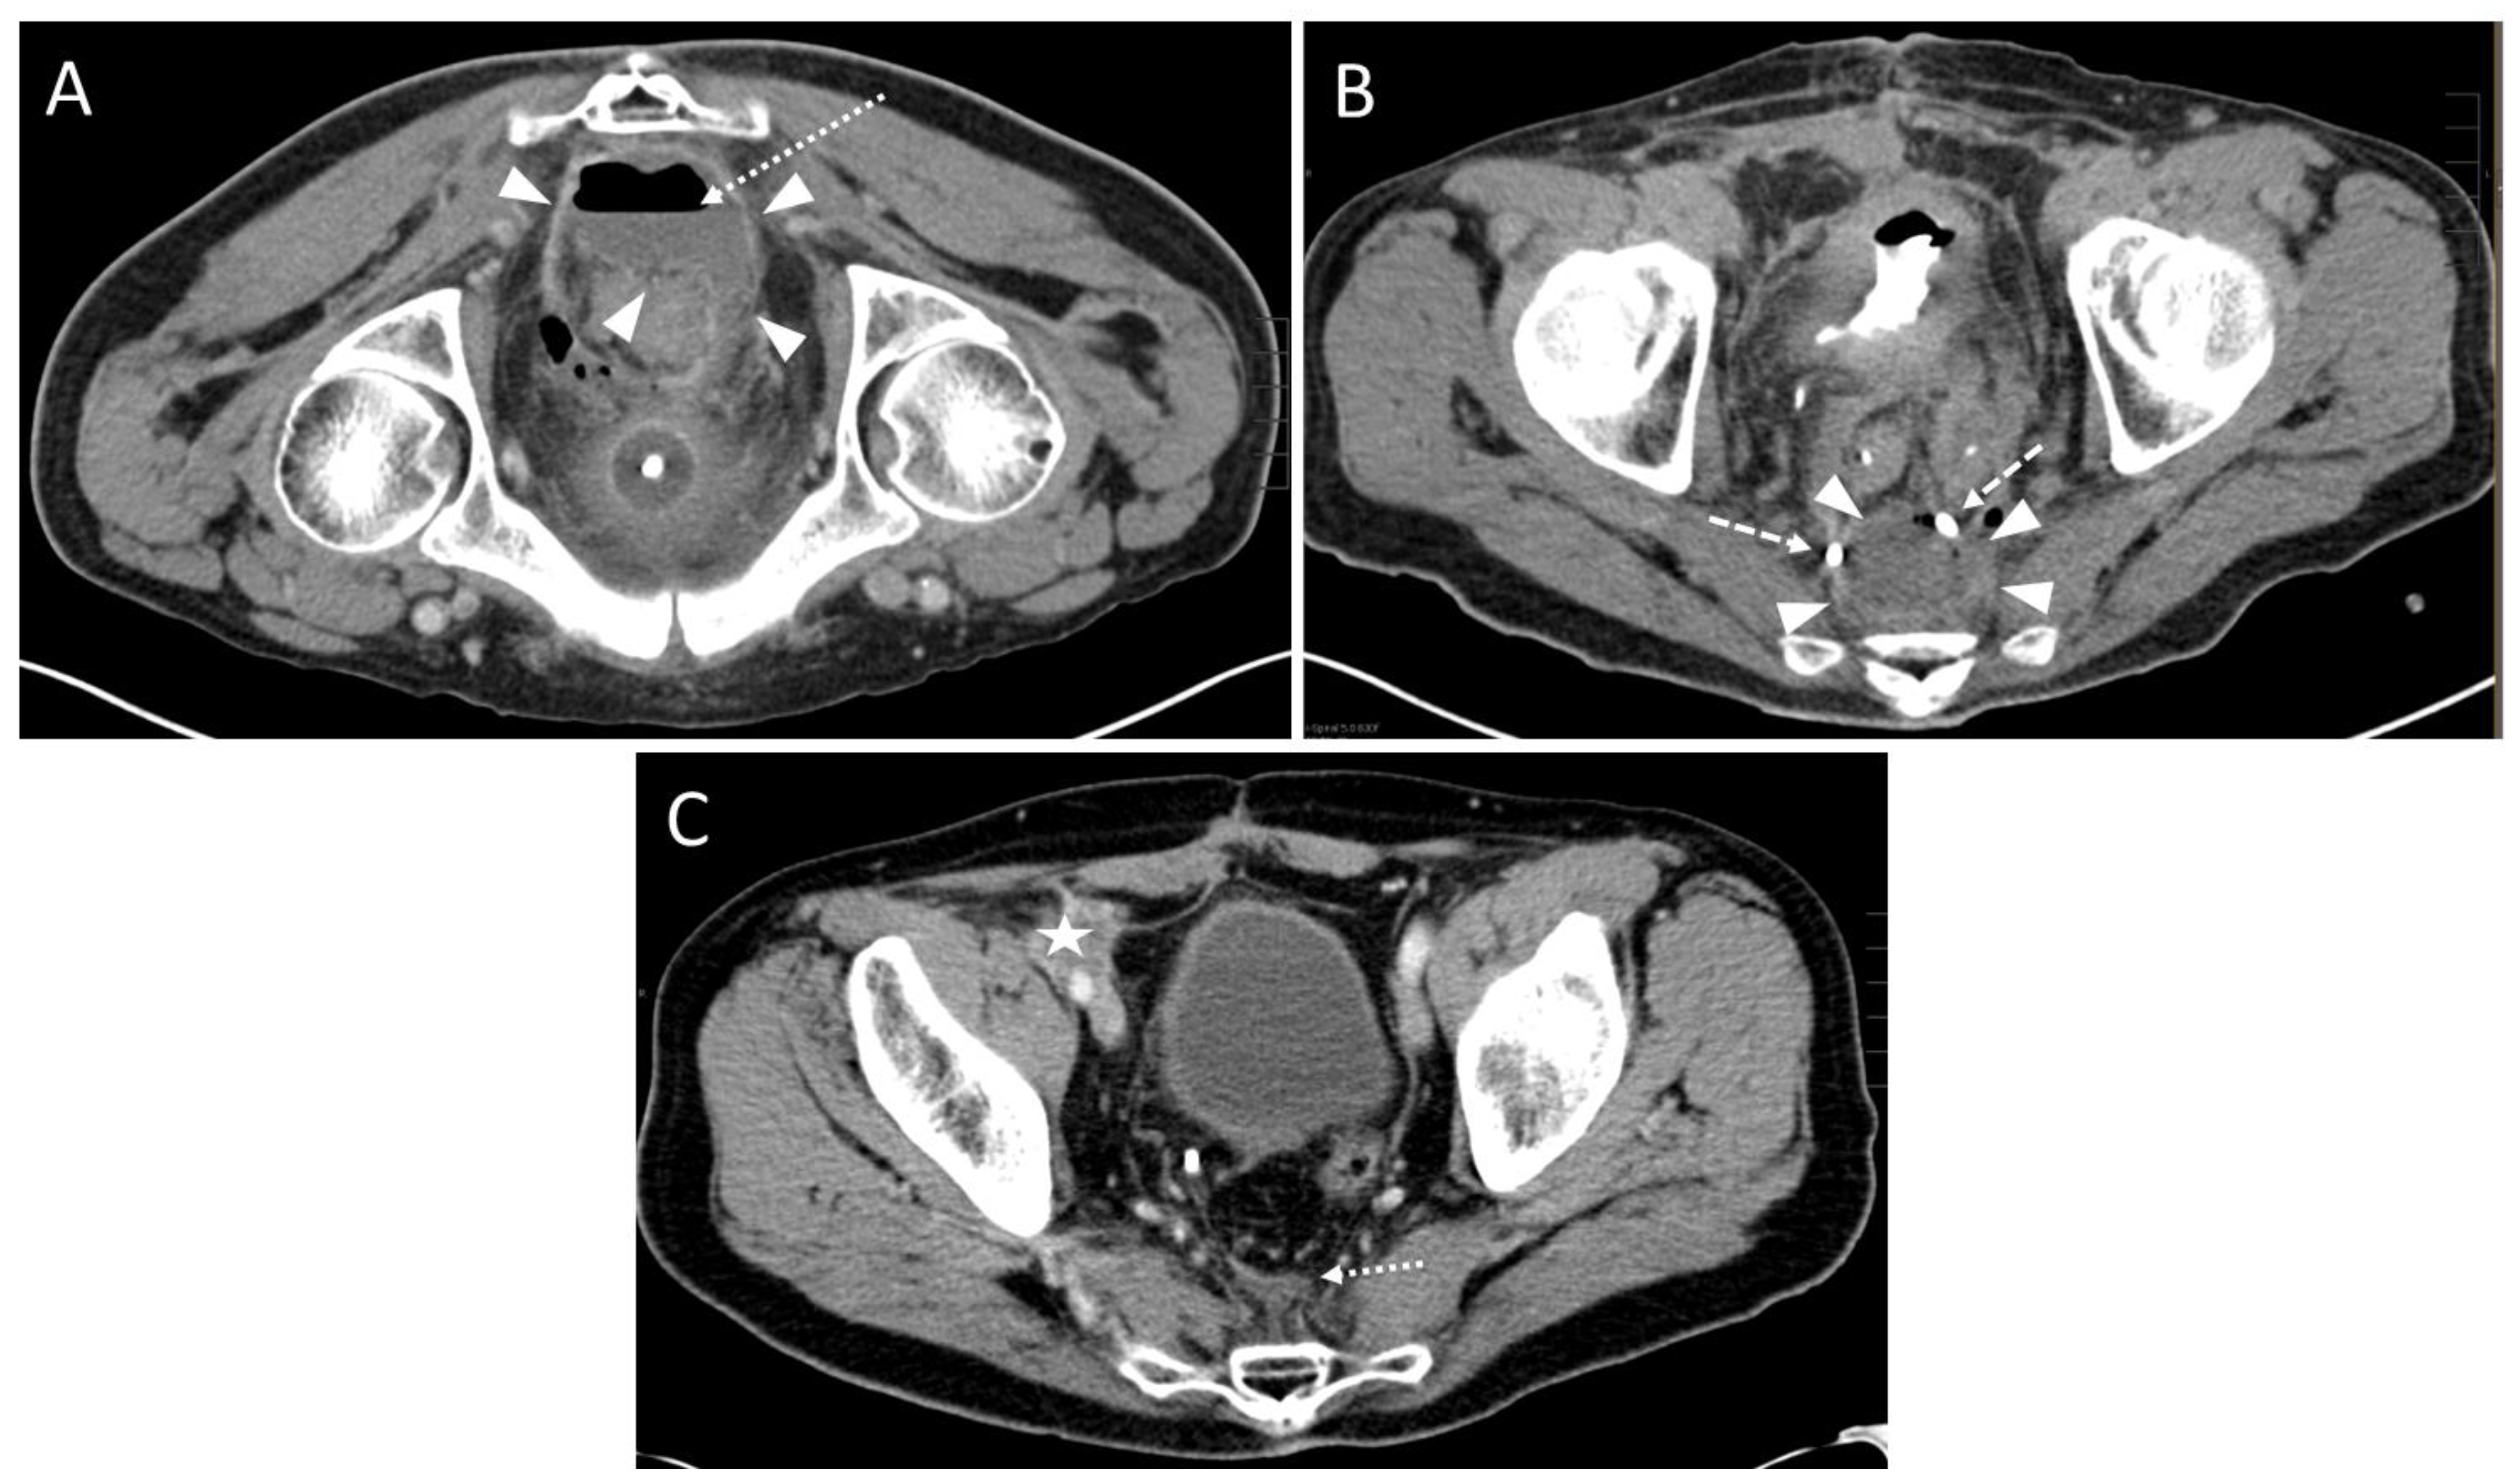

3.2. Pre- and Peri-Interventional Analysis

| Predominant location of the fluid collection | Count |

| presacral | 39 (97.5%) 3 |

| precoccygeal | 1 (2.5%) 3 |

| Approach | |

| parasacral | 29 (72.5%) 3 |

| paracoccygeal | 10 (25.0%) 3 |

| infracoccygeal | 1 (2.5%) 3 |

| Access path | Count |

| transpiriform | 8 (20.0%) 3 |

| infrapiriform | 31 (77.5%) 3 |